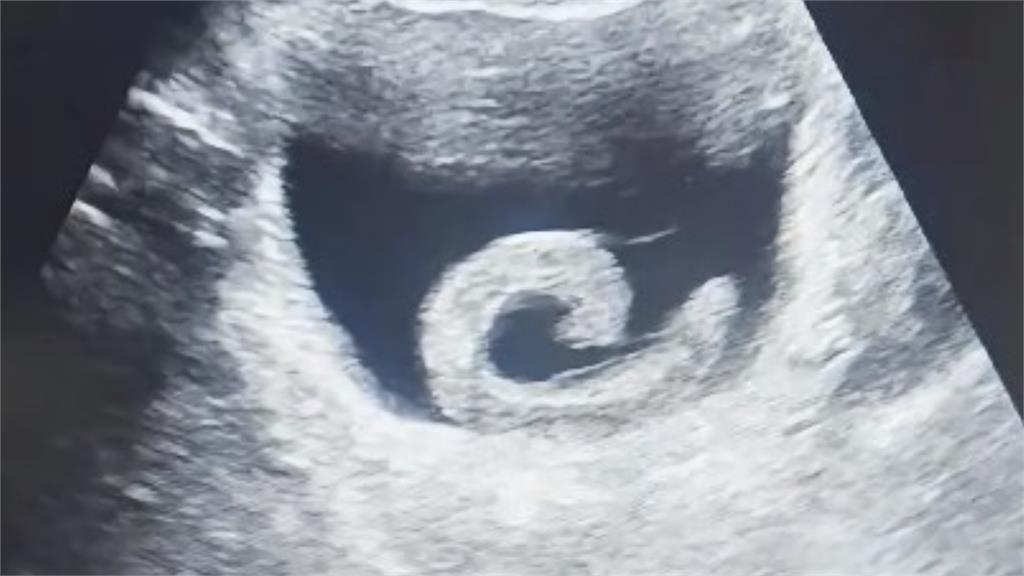

據中媒報導,這名居住在中國鄭州市的23歲男子,在將水蛭塞入體內時,還期待著某種「奇特」效果,但很快的,劇烈的疼痛感和排尿困難讓他從夢中清醒過來,並趕緊到醫院就診。經醫院檢查後發現,水蛭已順著尿道進到膀胱附著吸血,並分泌抗凝血物質,情況相當危急,醫師隨即進行手術,所幸手術過程順利,男子才得以脫離險境。男子事後坦言,原先對網路傳言抱有期待,沒想到竟演變成健康危機,對自己的魯莽行為感到無比懊悔。